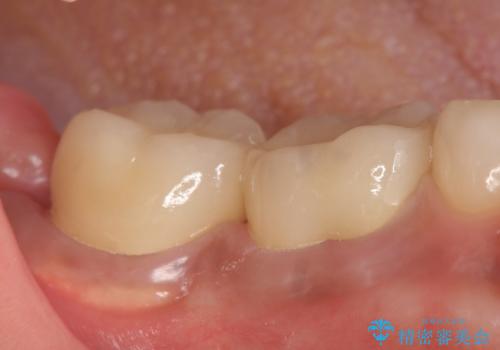

- 奥歯が欠けてしまったので診て欲しいといらっしゃった方の症例です。

再根管治療終了後、オールセラミッククラウンによる補綴を行いました。

今回用いたオールセラミッククラウンはジルコニアフレームという白い素材の上にセラミックを盛っているため、審美性が非常に高いのが特徴です。

また、ジルコニアは人工ダイヤモンドの材料にも使われているほど高い強度を持っており、そのためオールセラミッククラウンは審美性だけでなく、奥歯やブリッジの補綴も可能とするクラウンです。